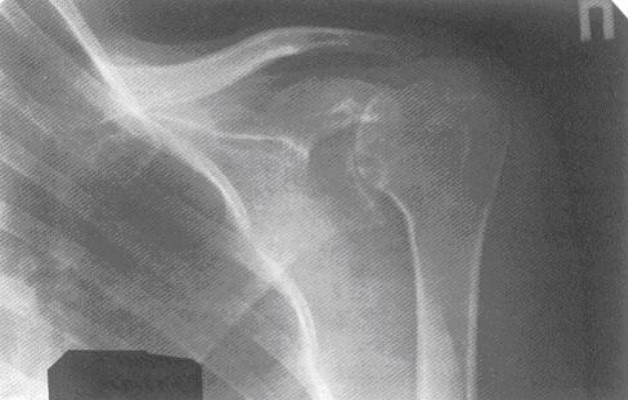

Рентгенологические симптомы

Важную роль в диагностике артрита любой этиологии играет рентген. Важно, чтобы врач, изучающий снимок, был компетентным. В противном случае больному будет поставлен неверный диагноз и назначено неправильное лечение. Важно не упустить время, не дать заболеванию перейти в хроническую форму, не дать человеку стать беспомощным инвалидом.

Симптомы артрита, которые видны на рентгеновском снимке:

- Костные деформации – заострения краев суставных поверхностей, неровность контуров, утолщение или истончение кости

- Эрозии – поражается как гиалиновый хрящ, покрывающий суставную головку, так и кость – в местах, где она не защищена хрящевой прослойкой.

- Сужение суставной щели. По рентгеновскому снимку можно установить степень артрита. На первой степени сужение минимальное, на третьей суставная щель практически отсутствует.

- Вывихи и подвывихи

- Остеопороз (снижение плотности костной ткани). Наблюдается в околосуставной области, но может быть и генерализованным.

- Изменения в мягких тканях – утолщения и уплотнения. Это самый ранний симптом артрита, видимый на рентгене. Он же является косвенным показателем развития синовита. Изменения в мягких тканях редко выявляются на рентгене. Для такой диагностики лучше подойдет магнитно-резонансная томография.

- Анкилоз (сращение костей) – наблюдается при четвертой степени артрита плечевого сустава. Суставная щель на рентгене не просматривается. Кости как бы «спаяны» между собой.

- Остеолиз («растворение» костной ткани без ее замещения – снижение количества остеобластов на фоне увеличения остеокластов). При артрите исчезает головка кости (эпифиз).

Рентгенологические симптомы по степеням

Выделяют 4 степени артрита. Симптомы нарастают постепенно, как по ощущениям, так и на рентгеновском снимке:

- 1 степень – околосуставной остеопороз слабо выражен. Незначительное сужение суставной щели.

- 2 степень – хорошо выраженный околосуставной остеопороз. Значительное сужение суставной щели. Единичные эрозии. Небольшая костная деформация суставных площадок.

- 3 степень – выраженный остеопороз, еще большее сужение суставной щели, множественные эрозии, сильные костные деформации. Возможен подвывих и вывих плечевого сустава.

- 4 степень – к околосуставному остеопорозу присоединяется распространенный (не всегда). Обширная эрозия, сильные костные деформации, субхондральный остеосклероз. Наблюдается сращение суставных поверхностей (анкилоз). Остеофиты явно выражены.